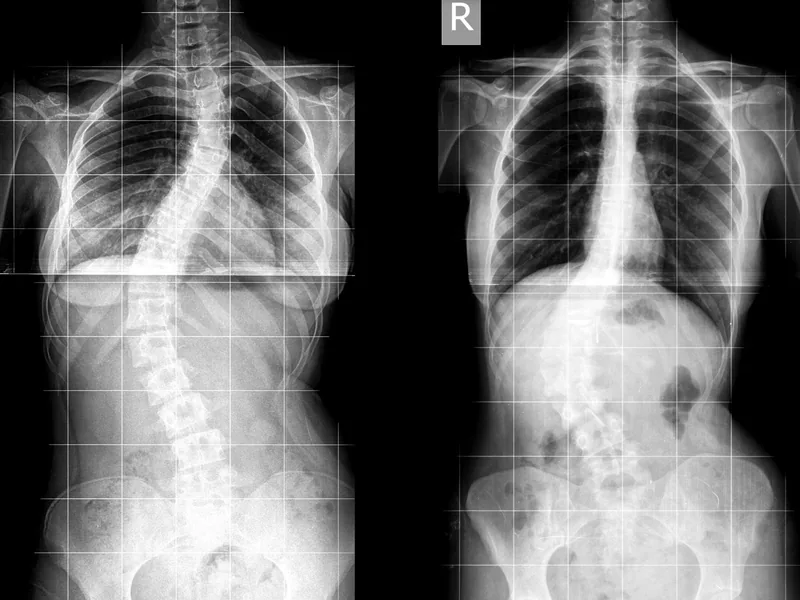

側弯症の背骨レントゲン画像